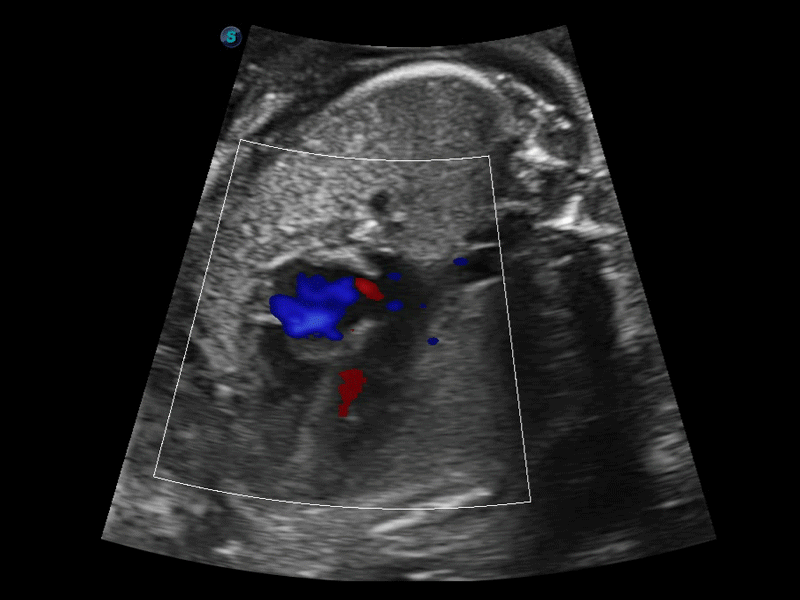

開立醫(yī)療通過不斷的技術(shù)創(chuàng)新,為大眾的生命健康提供持續(xù)關(guān)愛。P12 Plus采用全新一代超聲成像平臺,新平臺旨在將真實還原組織解剖結(jié)構(gòu)作為首要目標(biāo)。平臺采用全新集成化硬件模塊,搭載新一代芯片,系統(tǒng)性能得到大幅提升,為您的診斷提供了豐富的臨床信息。優(yōu)異的圖像表現(xiàn),豐富的探頭配置,全面的應(yīng)用功能,為您日常診斷提供了可靠的助手。

彩色多普勒超聲診斷系統(tǒng)